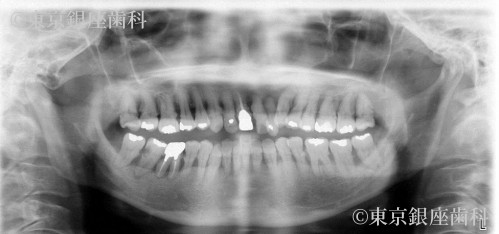

歯の揺れがひどくまともな食事がとれず口腔内の悩みにより鬱傾向。

半年で急激に歯周病が進み、それまで頻繁に行っていた友人とのランチや家族とのお出かけも出来なくなり引き篭もるようになった。

歯の揺れがひどくまともな食事がとれない。

歯周病の進行により歯に動揺があり長期の保存が難しく、臼歯の欠損で咬み合わせが下がって前歯部への負担が大きくなっているため全顎的な治療が必要と判断し上下顎でワンデイインプラントを行うことにした。